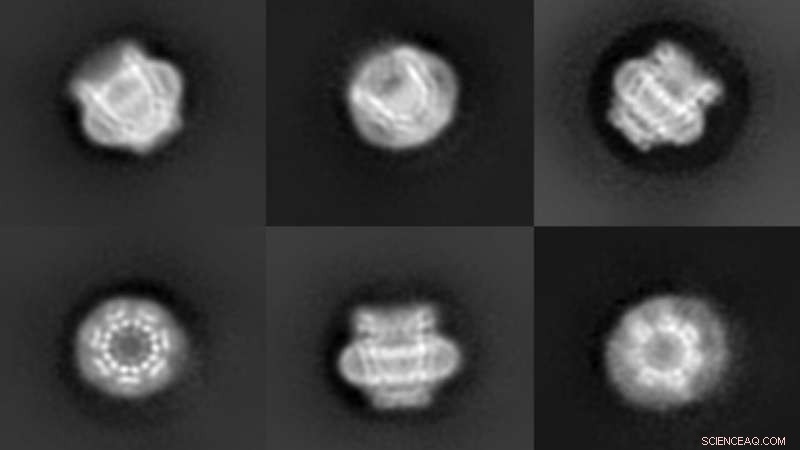

Six microscopic views of the 3D pore protein pannexin 1. The images were captured using cryo-electron microscopy. Each pore protein is about 6 nm wide. This means that well over 300,000 could fit on the head of a pin (2 mm). Credit: Furukawa lab/CSHL, 2020

Michalski and Johanna Syrjanen, also in the Furukawa lab at CSHL collaborated with the Kawate lab at Cornell University, and published their findings in the journal eLife. They used a technique called cryo-electron microscopy (cryo-EM) to capture a half-million images of a pannexin pore, called "pannexin 1," from many different angles. They then merged the images to form a three-dimensional model. Pannexin 1 is made up of seven identical proteins in a donut-like ring around a central pore.